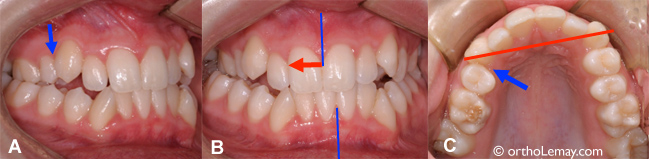

(A et B) Cette jeune femme de 19 ans s’est fait extraire une prémolaire inférieure gauche (à l’endroit indiqué par les flèches bleues) dans le but d’aider la canine à sortir. Bien que ceci ait facilité l’éruption de la canine, l’effet fut désastreux sur l’alignement des dents qui ont dévié vers la gauche (flèches rouges), causant une importante asymétrie des lignes médianes (lignes bleues = milieu de chaque arcade dentaire). (C) Une ligne passant par les 2 canines inférieures montre l’importante asymétrie qui s’est développée à la suite de la migration des dents dans l’espace créé par l’extraction de la prémolaire. (Femme – 19 ans)

Lorsqu’une telle extraction est envisagée, il est quand même indiqué de préserver l’espace à l’aide d’appareils orthodontiques pour guider l’éruption des dents et prévenir des mouvements dentaires indésirables qui occasionneront d’autres problèmes.